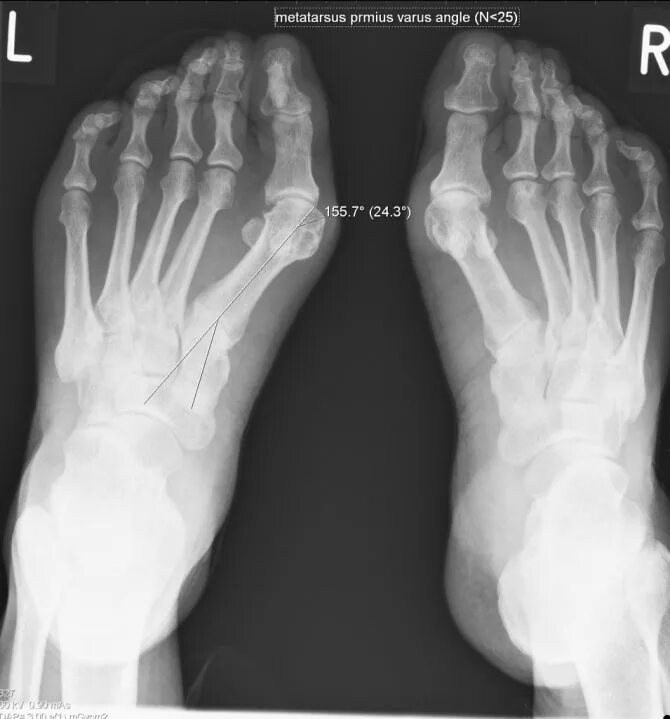

Степени вальгусной деформации